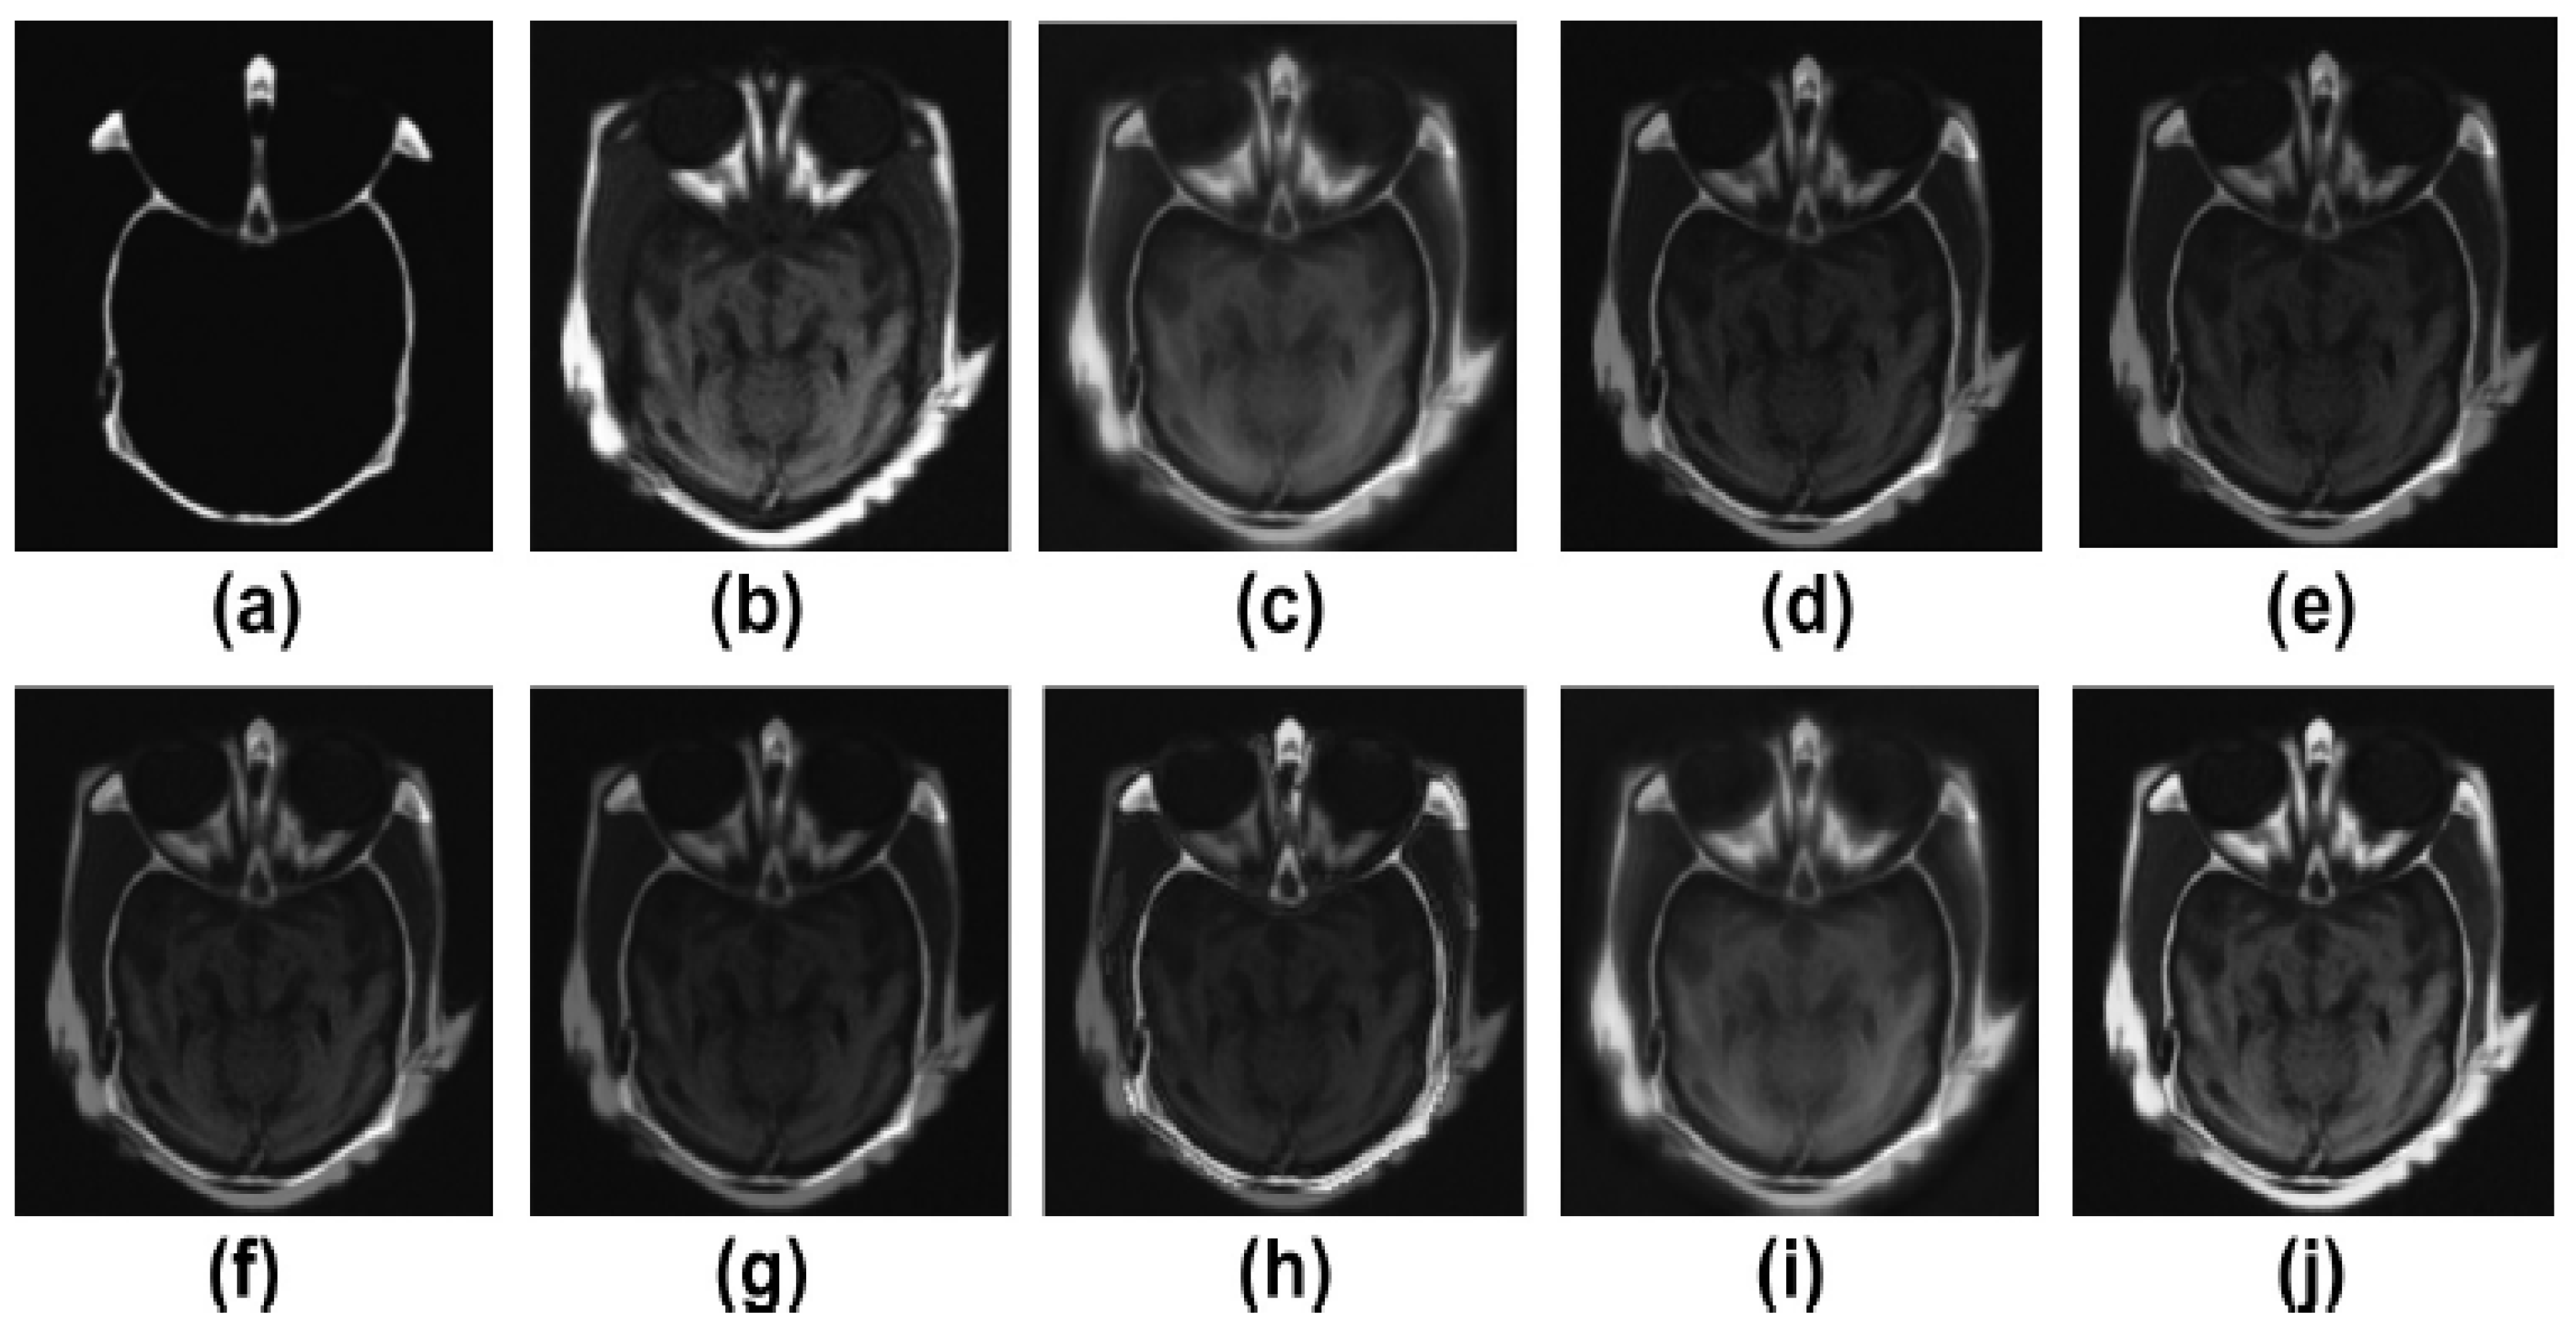

5. Experimental Results

5.2. Results and Discussion